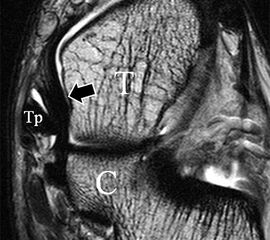

Man unterscheidet bei dem Ligamentum deltoideum eine tiefe Schicht (Pars tibiotalare posterior, Pars tibiotalare anterius) und eine oberflächliche Schicht (Pars tibionaviculare, Pars tibiocalcaneare, Pars tibiotalare posterius superficialis und Tibiospring-Ligament) 10. Hochauflösende Techniken lassen eine differenzierte Beurteilung aller Bandanteile zu. Sowohl rein ligamentäre als auch osteo-ligamentäre Ausrisse sind normalerweise gut zu erkennen. Die Pars tibiotalaris posterior ist multifaszikulär aufgebaut und sowohl axial als auch coronar (Abb. 19 a) gut bildgebend abzugrenzen. Die deutlich kleinere, nur inkonstant angelegte Pars tibiotalare anterior inseriert an einem kleinen Talustuberkel (Abb. 19 b). Ossäre Bandausrisse kommen hier gehäuft vor. Proximal verlaufen die Pars tibiocalcaneare und die Pars tibionaviculare gemeinsam (Abb. 19 c) nach kaudal und trennen sich dann in zum Calcaneus und zum Os naviculare ziehende Bündel auf. Ein besonderer Typ ligamentärer Verbindungen stellt das Tibiospring-Ligament dar. Es verbindet nicht wie für Ligamente typisch zwei Knochen miteinander, sondern es hat seinen ossären Ursprung an der Tibia und inseriert am Pfannenband (Ligamentum calcaneonaviculare plantare, im englischen Schrifttum Spring-Ligament genannt), also nicht ossär. Das Innenband ist mit 60% der Verletzungen am häufigsten betroffen. Isolierte Innenbandverletzungen sind jedoch selten. Sie treten gehäuft assoziiert mit Syndesmosenläsionen, Fibulafrakturen, Verletzungen des Muskulus tibialis posterior und des Pfannenbandes auf (H.-K. Beyer 2003). Entsprechend sollte auf diese Kollateralverletzungen bei der Beurteilung geachtet werden. Eine weitere Folge von Verletzungen des Ligamentum deltoideum ist die chronische Sprunggelenksinstabilität. Arthroskopisch weisen hier bis zu 40% der Patienten einen elongierten Verlauf des Ligamentum deltoideum auf. In diesem Patientenkollektiv besteht auch eine erhöhte chondrale Komorbidität mit arthroskopisch erkennbaren Knorpelschäden (98%) im Gegensatz zu der Patientengruppe (66% Knorpelschäden) mit reiner Außenbandinstabilität 11. Dies belegt die klinische Bedeutung von Innenbandverletzungen.